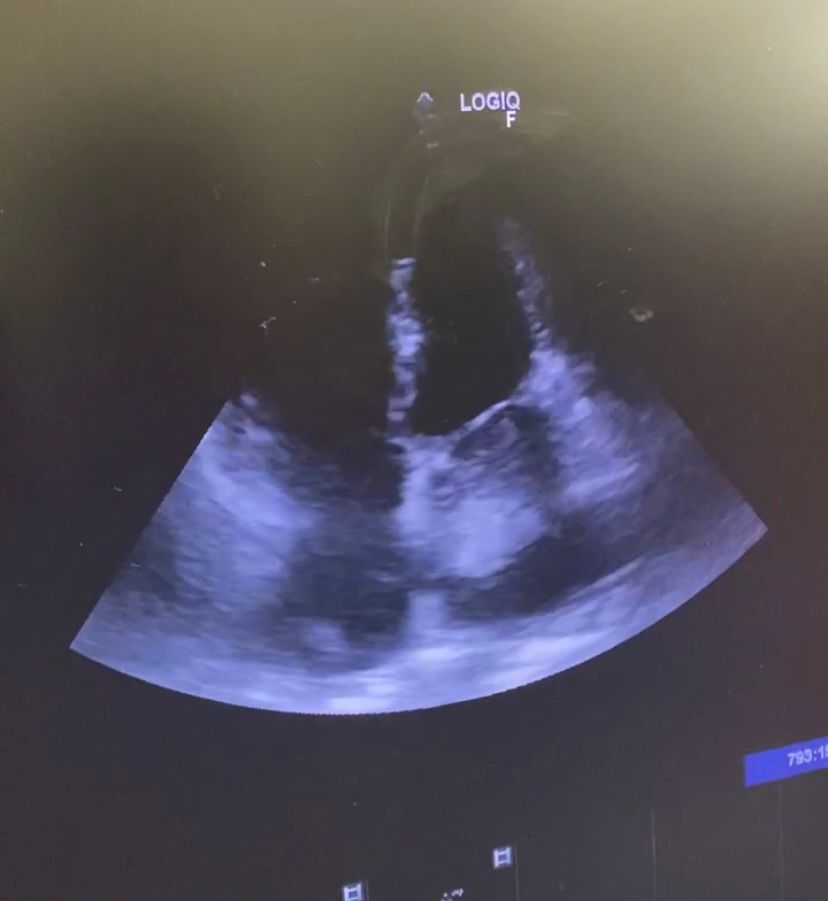

Se realiza ecografía trastorácica a pie de cama objetivándose gran masa a nivel de aurícula izquierda compatible con Mixoma auricular que protruye hacia válvula mitral generando obstrucción severa confirmándose en ecografía reglada posterior.

Juicio clínico: Mixoma auricular izquierdo de gran tamaño.

Diagnóstico diferencial: estenosis mitral.